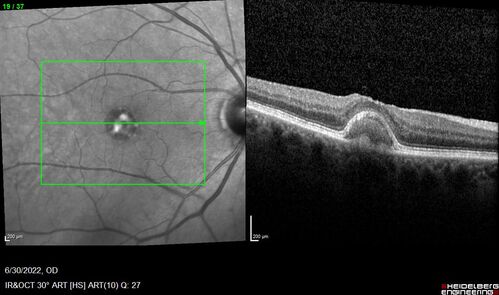

Pattern Dystrophy with Collapsed Vitelliform

74 year old female with vision loss in eye with collapsed vitelliform lesion.